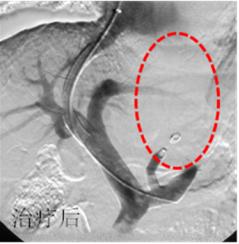

发现血压升高5年,两种降压药物不能控制。造影发现右侧肾动脉重度狭窄。

治疗前

介入治疗后肾动脉狭窄消失,血压恢复正常。

治疗后